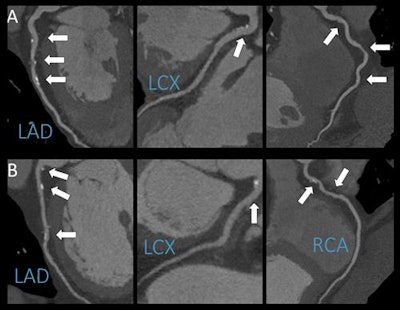

"CCTA is an excellent diagnostic modality to noninvasively depict the coronary wall and identify atherosclerotic lesions," Karády said. "Furthermore, we're able to characterize plaques and differentiate between several types. Prior studies used cardiovascular risk factors -- like high cholesterol levels -- and cardiovascular outcomes to study the effects of alcohol, but our study is unique in that we analyzed both drinkers and nondrinkers using CCTA, which may shed some light on how alcohol may or may not contribute to the development of fatty plaques in the arteries of the heart."